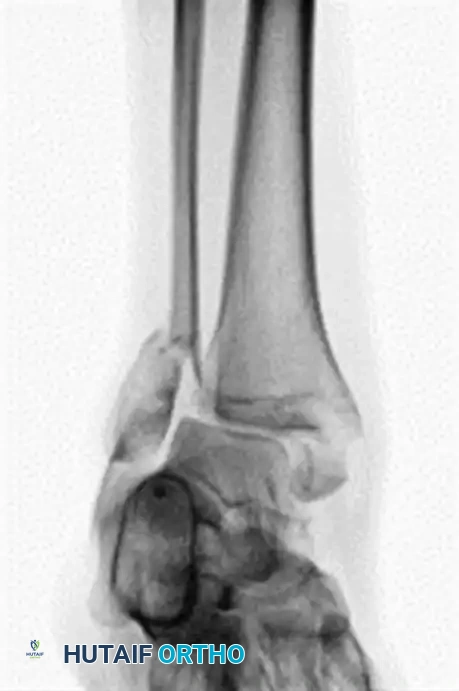

FIGURE 85-25 C-E: Postoperative fixation demonstrating robust fibular plating, medial malleolar screw fixation, and critical supplemental syndesmotic screws to reinforce the mortise.